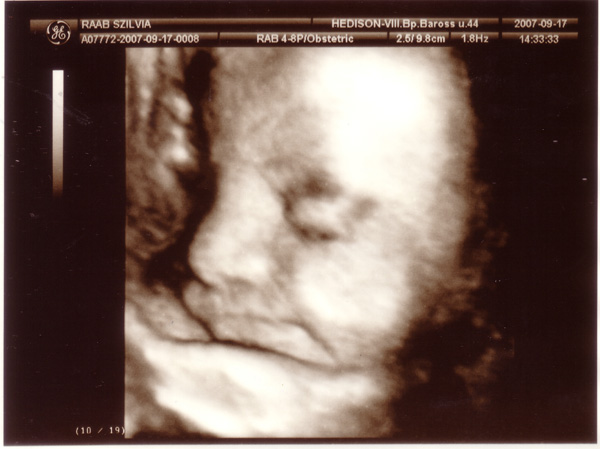

Voltam az otthoni nődokimnál, illetve a Kristóf gyerekdokijánál, mindkettő NAGYON, DE NAGYON MEGNYUGTATÓ VOLT számomra 8) Annyira éreztem, hogy "jó kezekben" vagyunk :wink: Voltunk 4D-s UH-n is, amit nagyon élveztünk szintén, de már nem látszott annyira jól a kisMütyür, ami természetes is, de sikerült egy nagyon jó képet csinálni róla, ezt fel is teszem:

Kép